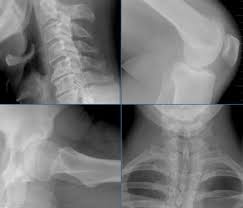

Skoliose Symptome Und Behandlung Ndr De Ratgeber Gesundheit

Skoliose Symptome Und Behandlung Ndr De Ratgeber Gesundheit from www.ndr.de. Klick hier um mehr zu erfahren!